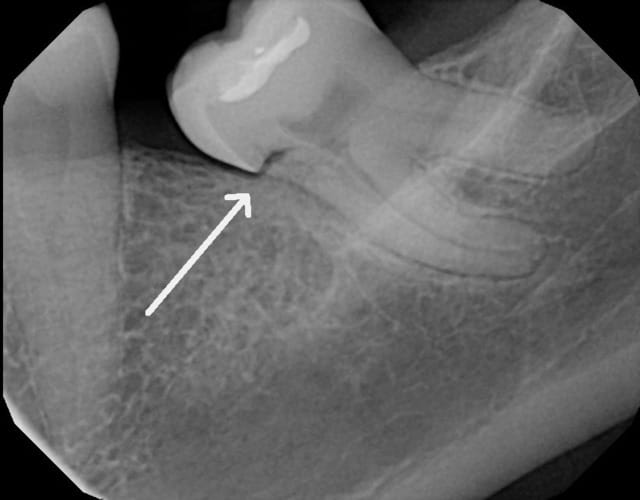

j'ai un patient qui vient en consultation pour ce que je croyait n'être qu'une simple mylolyse. douleur lors du brossage, petits chocs éléctriques, ...mais aussi douleur avec le sucre (inhabituel pour les mylolyses).

je fais une radio, et là.! voici ce qu'on trouve; une jolie cavité dans laquelle la sonde pénètre bien facilement.

Si ça se trouve, ce n'est pas une carie, mais une résorption externe. Il est possible qu'elle communique avec la pulpe, donc, on connaît la suite.

Le pb n'est pas de savoir avec quoi restaurer, le pb est d'abord d'apprécier l'étendue de la lésion et d'en tirer les conséquences.